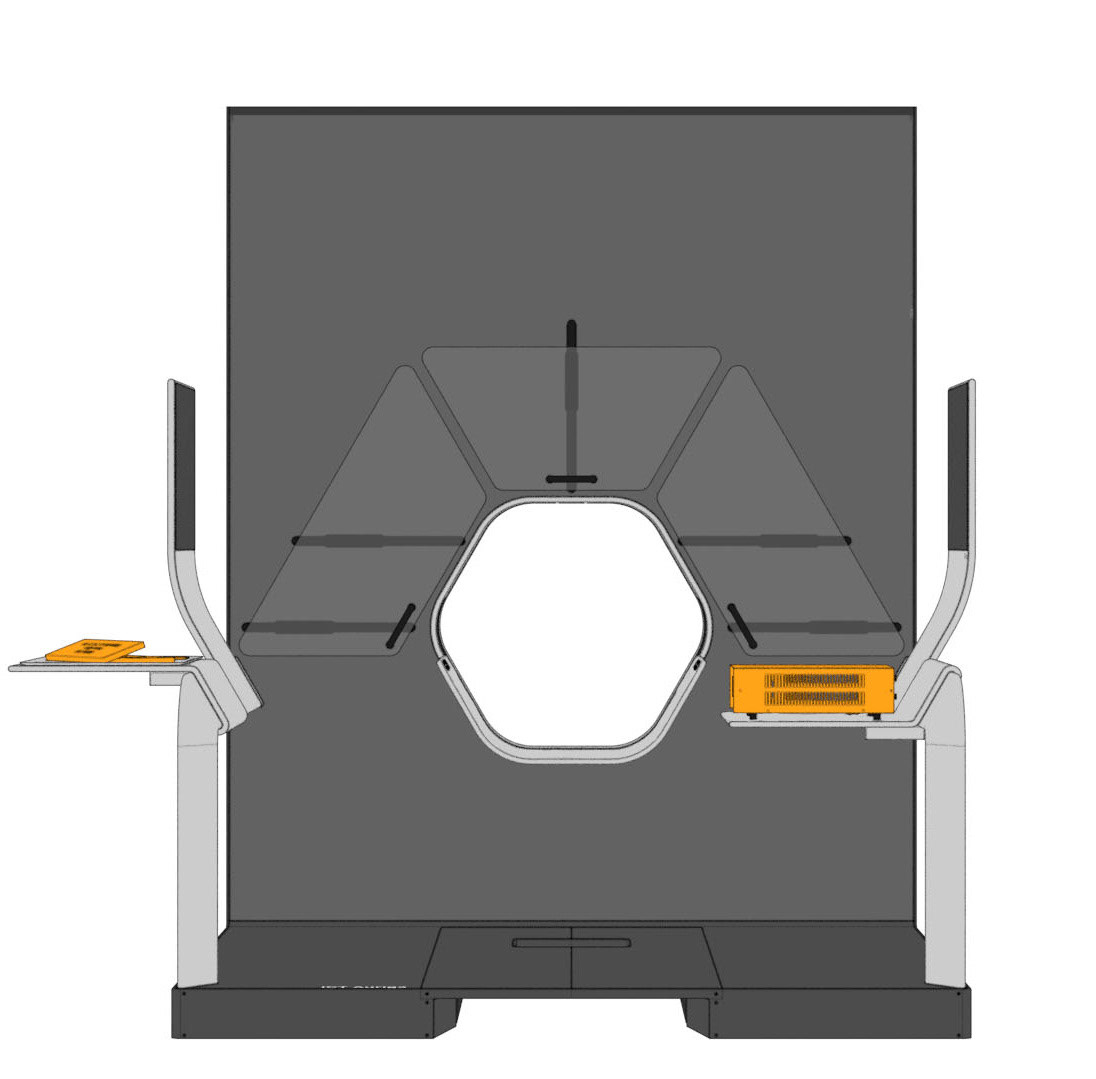

Auriga is an architecturally inspired CT device. The gantry extends to the ceiling and becomes a spatial installation. This takes away its massive “machine-character” and makes it part of the room. The gantry height is individually adapted to the given space - individuality becomes part of the product. In order to enable right- and left-handed working, the overall construction is symmetrical and intervention from both sides is equally possible.

The central design feature is the hexagonal gantry opening. It provides space for the lamps and displays. The large fronts of the gantry offer space for a display of different coloured patterns and animations, which visualize the radiation. These can be individually selected and adapted together with the overall height of the gantry. The patterns pick up on the hexagonal shape of the gantry opening and set it off. To protect the interventionists from radiation, lead glass panels and a radiation protection tray are installed. The sliding lead glass panels allow individual adaptation to the patient and the interventionists working space. The tray serves to protect the abdomen and offers a lot of foot space as well as a front leaning aid for a safe stand.

For direct inspection of the CT scans, there is one large overview screen per side and a small detail screen inside the gantry. The control interface of the gantry is located inside the lower trough, which protects the abdomen of the interventionists from radiation. In addition, there is a foot pedal on the floor that allows hands-free activation of the CT imaging.

Various tables can be suspended on the railing. This enables the individual positioning of surgical instruments and devices. To relieve the interventionists, it is also possible to lean against the railing, similar to a standing seat in a gondola or tram. In addition, the railing offers protection against a potential fall from the platform.